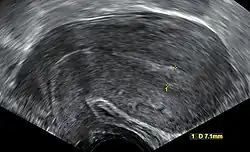

An ultrasound showing a gestational sac containing a yolk sac but no embryo

A review article in The New England Journal of Medicine based on a consensus meeting of the Society of Radiologists in Ultrasound in America (SRU) has suggested that miscarriage should be diagnosed only if any of the following criteria are met upon ultrasonography visualisation:[110]

Miscarriage diagnosed Miscarriage suspected References

Crown-rump length of at least 7 mm and no heartbeat. Crown–rump length of less than 7 mm and no heartbeat. [110][111]

Mean gestational sac diameter of at least 25 mm and no embryo. Mean gestational sac diameter of 16–24 mm and no embryo. [110][111]

Absence of embryo with heartbeat at least 2 weeks after an ultrasound scan that showed a gestational sac without a yolk sac. Absence of embryo with heartbeat 7–13 days after an ultrasound scan that showed a gestational sac without a yolk sac. [110][111]

Absence of embryo with heartbeat at least 11 days after an ultrasound scan that showed a gestational sac with a yolk sac. Absence of embryo with heartbeat 7–10 days after a scan that showed a gestational sac with a yolk sac. [110][111]

Absence of embryo at least 6 weeks after last menstrual period. [110][111]

Amniotic sac seen adjacent to yolk sac, and with no visible embryo. [110][111]

Yolk sac of more than 7 mm. [110][111]

Small gestational sac compared to embryo size (less than 5 mm difference between mean sac diameter and crown-rump length). [110][111]